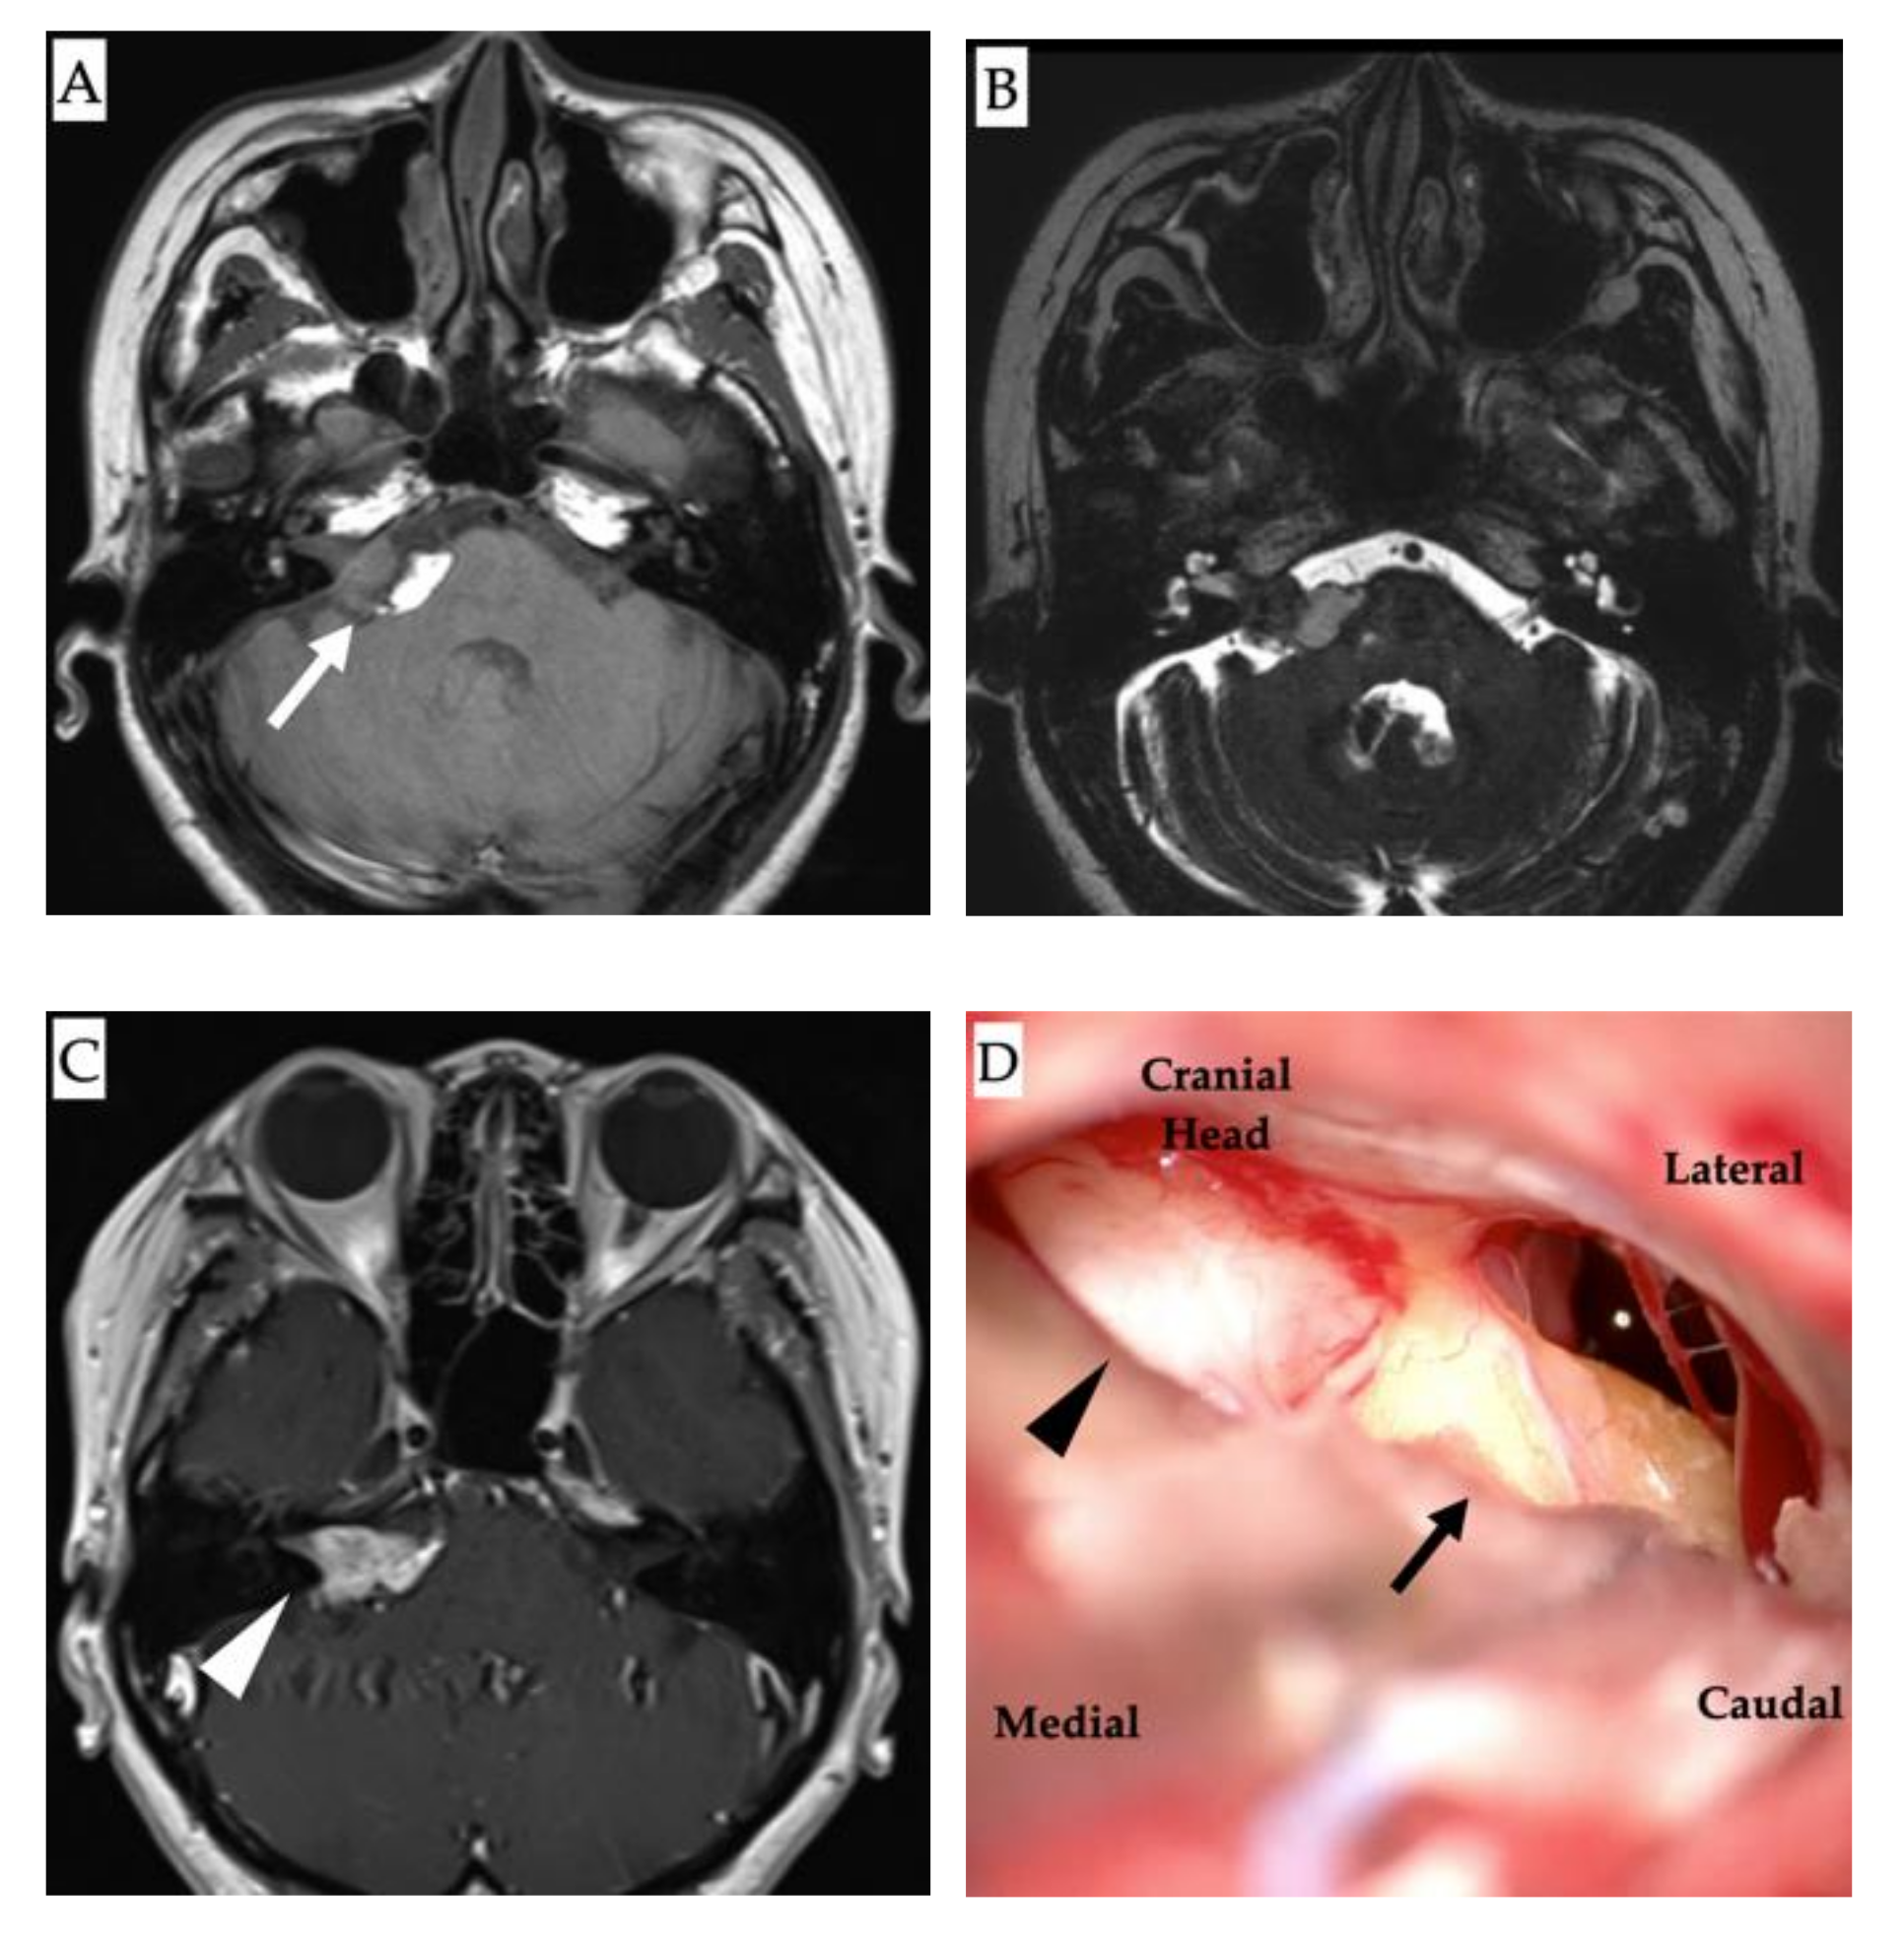

2. Case Presentation